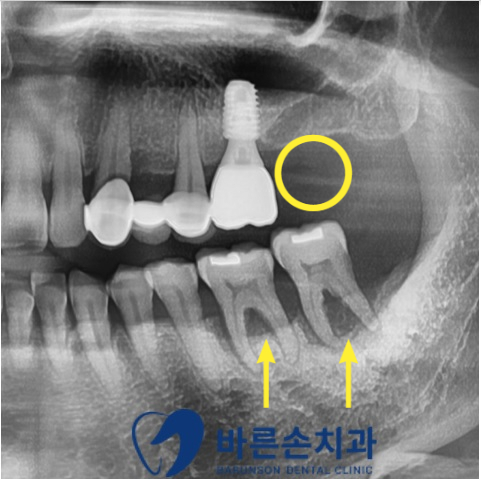

먼저 치아와 주변 뼈(치조골)의 상태를 자세히 확인하기 위해 파노라마 촬영을 시행했습니다.

파노라마 사진을 확인해 보니 위에는 치아가 상실되어 있고

아래는 치아를 잘 잡아주는 잇몸뼈(치조골)가 소실되어 흔들리고 있는 상태였습니다.

위에는 <상악동 거상술> 이라는 수술이 추가로 필요합니다.

뼈가 최소 7~8mm 정도가 있어야 하는데

이 환자분의 경우, 위쪽 치아가 없는 부위의 뼈 길이가 4~5mm 정도 밖에 안되기 떄문이죠